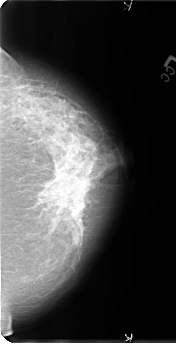

B_3128_1.RIGHT_CC

RIGHT_CC LINES 4792 PIXELS_PER_LINE 2664 BITS_PER_PIXEL 12 RESOLUTION 50 OVERLAY